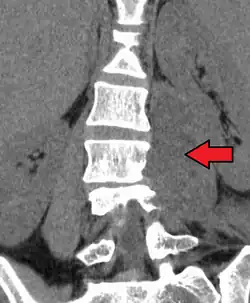

Paraspinal abscess in the psoas muscle

Psoas abscess is a collection of pus (abscess) in the iliopsoas muscle compartment.[1][2][3] It can be classified into primary psoas abscess (caused by hematogenous or lymphatic spread of a pathogen) and secondary psoas abscess (resulting from contiguous spread from an adjacent infectious focus).[3]